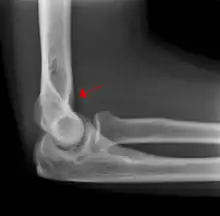

A subtle radial head fracture with associated positive sail sign

The fat pad sign, also known as the sail sign, is a potential finding on elbow radiography which suggests a fracture of one or more bones at the elbow. It is may indicate an occult fracture that is not directly visible. Its name derives from the fact that it has the shape of a spinnaker (sail).[1] It is caused by displacement of the fat pad around the elbow joint. Both anterior and posterior fat pad signs exist, and both can be found on the same X-ray.

The fat pad sign is invaluable in assessing for the presence of an intra-articular fracture of the elbow. An anterior fat pad is often normal. However a posterior fat pad seen on a lateral x-ray of the elbow is always abnormal. The patient will be unable to flex their elbow and requires orthopaedic input.[2]